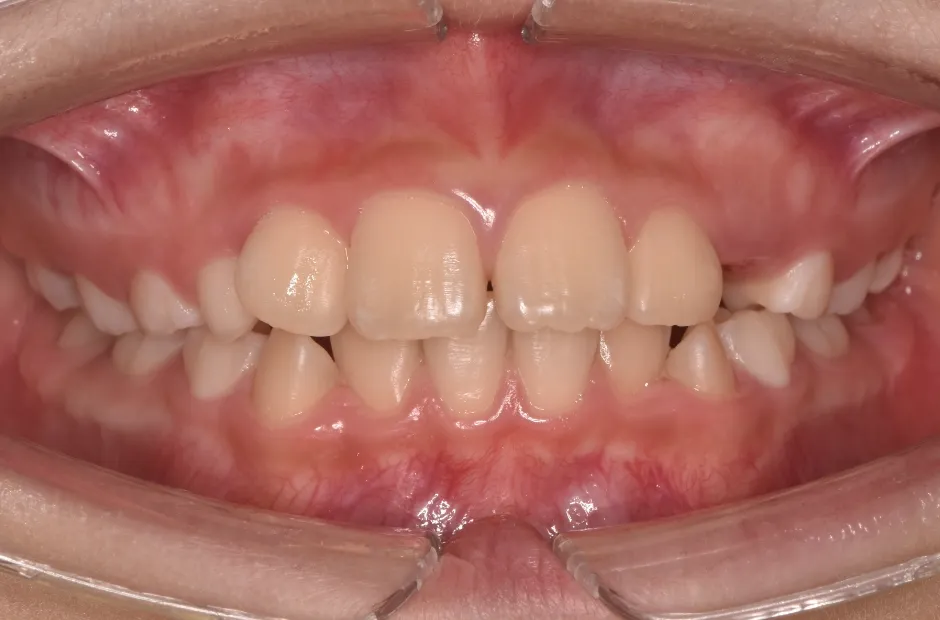

治療症例

ブラケット矯正

前歯部反対咬合

| 診断名・主訴 | 前歯部反対咬合 |

|---|---|

| 年齢・性別 | 14歳・男性 |

| 治療期間・回数 | 1年2か月 |

| 治療に用いた主な装置 | ブラケット矯正 |

| 抜歯部位 | なし |

| 治療費 | 60万円(税抜) |

| リスク・副作用 | 装置による違和感・疼痛・歯肉退縮・歯根吸収・虫歯のリスクなど |

治療前

治療後